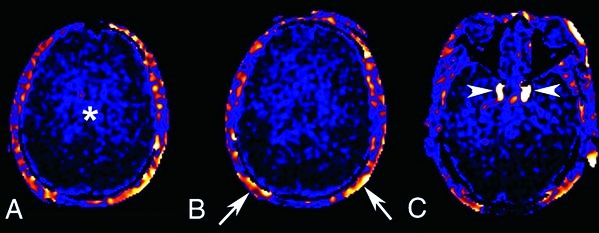

Умеренные диффузные изменения белого вещества головного мозга (БЭА) могут свидетельствовать о различных патологиях, включая сосудистые заболевания, демиелинизирующие процессы и возрастные изменения. Врачи отмечают, что такие изменения часто сопровождаются симптомами, такими как головные боли, снижение когнитивных функций, ухудшение памяти и внимание. Для диагностики используются методы нейровизуализации, такие как МРТ, которые позволяют визуализировать изменения в структуре мозга. Лечение зависит от причины изменений и может включать медикаментозную терапию, физиотерапию и изменение образа жизни. Важно, чтобы пациенты своевременно обращались к специалистам, так как ранняя диагностика и адекватное лечение могут значительно улучшить качество жизни и замедлить прогрессирование заболеваний.

- магнитно-резонансная томография;

На МРТ пациента отправляют, если зафиксирована повышенная электрическая активность. Она свидетельствует о наличии патологии, которая будет заметна на томографическом снимке.